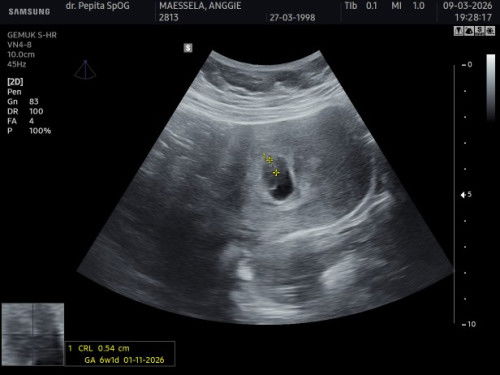

Dari kemarin mau USG maju mundur karena takut belum kelihatan, alhasil karena pengen dapet vitamin juga memutuskan usg. Diliat dari hasil USG kisaran 6-7 week dan Alhamdulillah udah ada detak jantungnya. Perkiraan HPL 1 november. Semangat buat para bunda semua 🫶🏻✨#firstmom #Sharingdong_Bund #askmommies